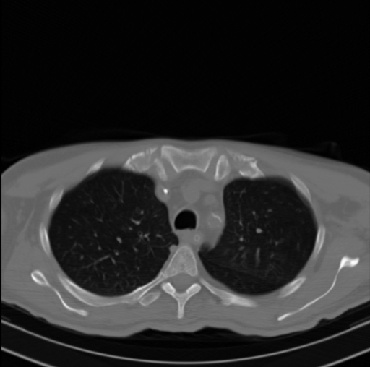

Early and reliable COVID-19 diagnosis based on chest 3-D CT scans can assist medical specialists in vital circumstances. Deep learning methodologies constitute a main approach for chest CT scan analysis and disease prediction. However, large annotated databases are necessary for developing deep learning models that are able to provide COVID-19 diagnosis across various medical environments in different countries. Due to privacy issues, publicly available COVID-19 CT datasets are highly difficult to obtain, which hinders the research and development of AI-enabled diagnosis methods of COVID-19 based on CT scans. In this paper we present the COV19-CT-DB database which is annotated for COVID-19, consisting of about 5,000 3-D CT scans, We have split the database in training, validation and test datasets. The former two datasets can be used for training and validation of machine learning models, while the latter will be used for evaluation of the developed models. We also present a deep learning approach, based on a CNN-RNN network and report its performance on the COVID19-CT-DB database.